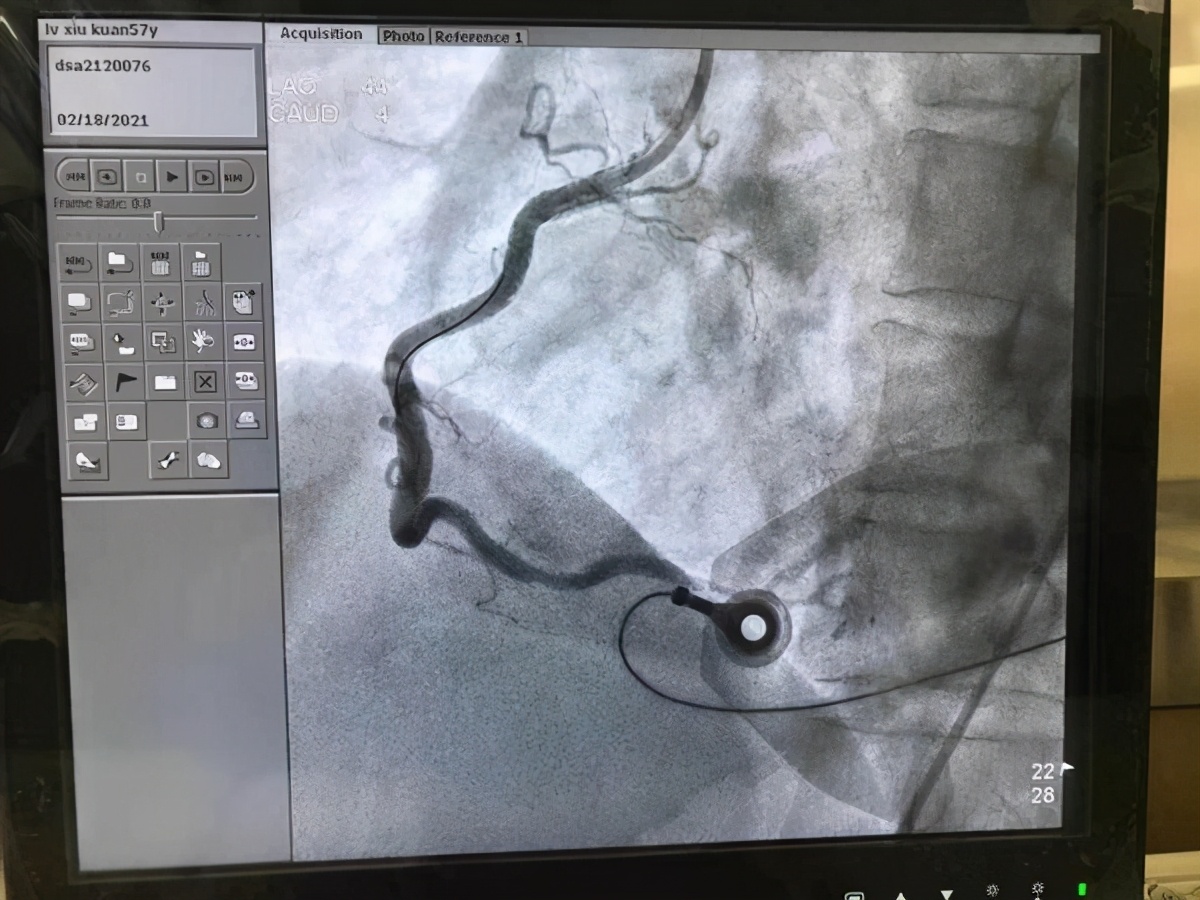

2月18日,正值农历正月初七,以往人流如织的医院少了往日的喧哗,但街头巷尾却依然少不了急救人忙碌如旧的身影。凌晨三点,沈阳急救中心皇姑二分中心翟宏广急救小组接到120指挥调度中心命令:“某医院急诊室有一心脏病患者需要转院。”急救小组闻讯迅速抵达现场,在现场与急诊医生沟通了解病情得知患者是急性下壁心梗,需要立即转往上级医院行介入治疗。

急救医生翟宏广一边准备好除颤仪监护仪,一边指导担架员搬抬患者。然而在转运的过程中,令翟宏广担心的事情还是发生了——患者突然出现双手握拳抽搐样动作,心电监护显示出现心室颤动,呼吸停止。翟宏广凭借专业意识临危不乱,立即呼叫并拍打患者的肩膀,但患者仍没有恢复意识,翟宏广迅速拿起除颤仪为患者除颤,护士李红旭遵照医嘱立即给予胺碘酮静脉推注。在大家的努力下,患者恢复了窦性心律和自主呼吸。算起来从患者出现心跳停止到复苏成功,只经过短短一分钟,一切发生得快速而惊险。待患者苏醒过来后,面对自己短暂的“断片”,他一脸茫然,并不知道自己在这短短的一分钟里竟与死神“擦肩而过”。

患者心跳呼吸恢复没多久,司机谢龙驾驶急救车便平稳地抵达医院,看似时间不长的转运,却让急救人员高度紧张。纵观整场急救,急救人员果断迅速进行的早期规范心肺复苏术对这次复苏发挥了重要作用,成功地帮助了患者恢复心跳、复律并维持稳定窦性心律。对于所有急救人员来说,帮助患者逃离死神魔爪,这不仅是单纯意义上的挽救一条生命,更是守护了一个家庭的完整与圆满。